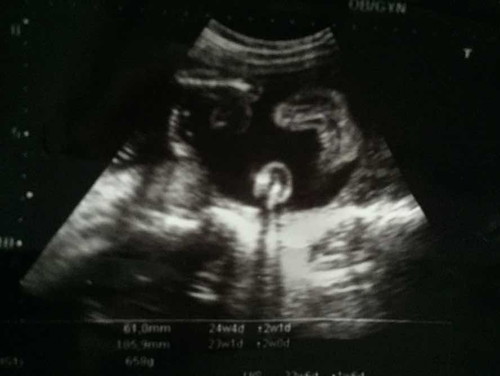

นี่เป็นรูประหว่างขาที่หมอซาวด์ให้ หมอบอกเป็นเพศหญิง แต่คนแก่หลายคนเห็น ท้อง สะดือ ทำนายฝัน และเอาความเชื่อโบราณ ทักว่าเป็นลูกผู้ชาย ช่วยดูยืนยันให้หน่อยได้มั้ยคะ ว่าน้องเป็นเพศไหน